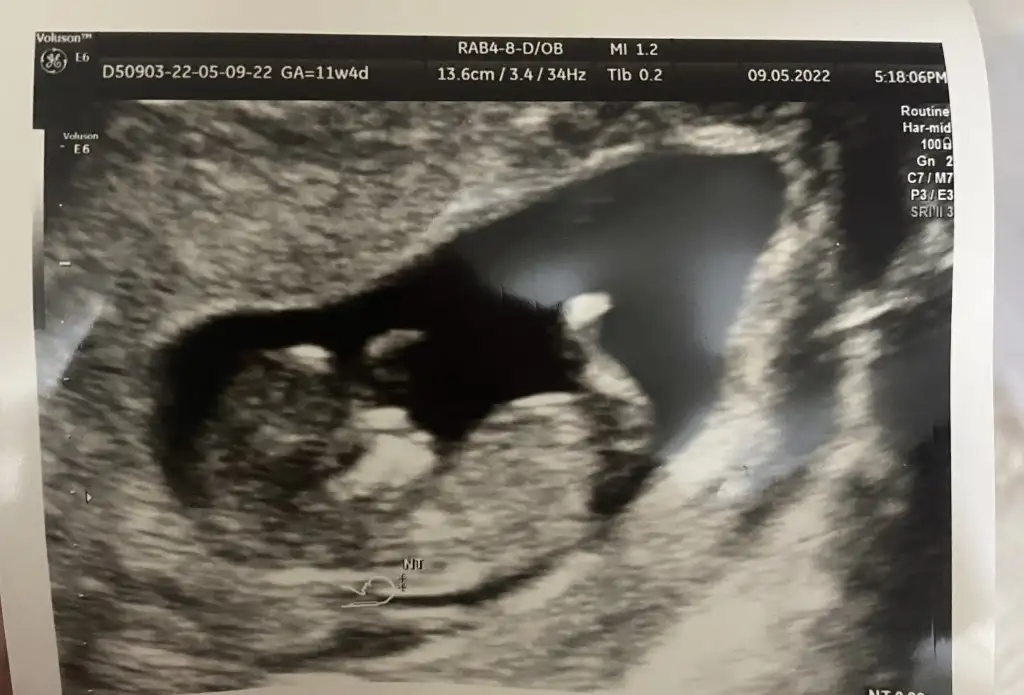

Kızlar merhabalar , bana da tahmin yapabilirmisiniz :) ve neye göre söylüyorsunuz onu da çok merak ediyorum yazarsanız çok sevinirim :) 11+4 üz

Eklentiler

• 6752E299-E085-4717-9F96-C78071E25EEC.webp

6752E299-E085-4717-9F96-C78071E25EEC.webp

32,9 KB · Görüntüleme: 142